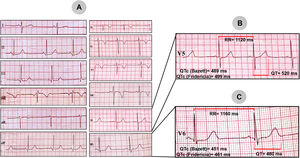

En el otro extremo del espectro clínico tenemos el caso 2; se trata de un niño de 5 años, sin historia familiar de eventos cardiovasculares, que lo llevan a consulta por 2 eventos de síncope en menos de 45 días, ambos durante el esfuerzo físico (corriendo). Se le evalúa con un ECG de 12 derivaciones (fig. 2A) que da como resultado (derivación V5) un intervalo de RR 1.120ms y un intervalo QT medido de 520ms (fig. 2B). El intervalo QTc se consideraría anormalmente prolongado por ambas fórmulas, por la de Bazett es de 489ms y con la fórmula de Fridericia tiene QTc de 499ms. Sin embargo, en la derivación V6 el intervalo QT medido es de 480ms, por lo que el QTc se consideraría limítrofe con ambas fórmulas: Bazett 451ms y Fridericia 461ms (fig. 2C). Esto resalta la necesidad de medirlo en la derivación donde el QT esté más prolongado. Debido a la bradicardia «relativa» para la edad y su efecto sobre la prolongación del intervalo QT, se decidió el implante de un marcapasos bicameral por vía epicárdica para aumentar la FC, con una evolución favorable hasta el momento.

A) Electrocardiograma de 12 derivaciones de un niño de 5 años, referido por antecedente de síncope. B) Magnificación de la derivación V5 con medición del intervalo QTc (489ms por la fórmula de Bazett y 499ms por la de Fridericia). C) Magnificación de la derivación V6 con medición del intervalo QTc (451ms por la fórmula de Bazett y 461ms por la de Fridericia).